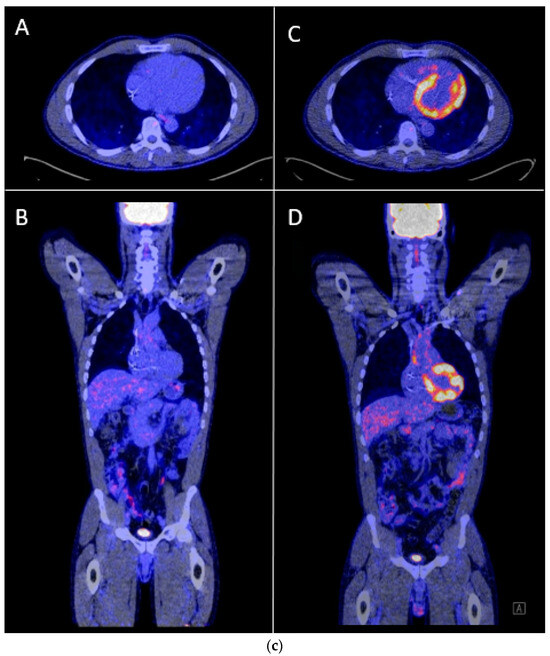

One of our cases was an adult patient with third-degree AV block caused by cardiac sarcoidosis, for which he had received a 2-lead ICD programmed in DDI-40 (dual-chamber pacing and sensing with inhibition, pacing both the atrium and ventricle, with a lower rate of 40 bpm). Over a period of seven years, remission was sustained, supported by 0% atrial or ventricular pacing and the absence of rhythm abnormalities. Subsequently, the patient presented with palpitations identified as recurrent AV block, leading to 100% ventricular pacing (Figure 5a,b). PET-CT imaging revealed a high suspicion of reactivation of cardiac sarcoidosis, with increased uptake of F-18 fluorodeoxyglucose (FDG) observed in the left ventricle, septum, and right ventricular free wall (Figure 5c). Following treatment with prednisone, remission was achieved, and the percentage pacing returned to 0%.

Figure 5.

(a) Development of atrioventricular (AV) block and ventricular pacing at lower rate. ECG Showing sinus rhythm at 80/min, third degree atrioventricular block, ventricular pacing at 30/min. (b) Device interrogation showing 100% ventricular pacing. Weekly percentage pacing and weekly heart rate, 1 year trend. A sudden rise to 100% pacing is seen. (c) F-18 FDG PET-CT whilst in remission versus recurrent episode of cardiac sarcoidosis. (A,B): F-18 FDG PET-CT transverse and coronal cross-sections showing no signs of active cardiac sarcoidosis. (C,D): F-18 FDG PET-CT transverse and coronal cross-sections showing high suspicion of reactivation of cardiac sarcoidosis with F-18 FDG uptake of the left ventricle and interventricular septum.